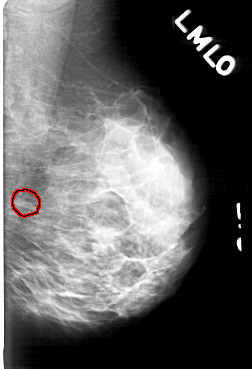

D_4171_1.LEFT_MLO

LEFT_MLO LINES 5161 PIXELS_PER_LINE 3526 BITS_PER_PIXEL 12 RESOLUTION 43.5 OVERLAY

FILE: D_4171_1.LEFT_MLO.OVERLAY

TOTAL_ABNORMALITIES 1

ABNORMALITY 1

LESION_TYPE CALCIFICATION TYPE ROUND_AND_REGULAR-PLEOMORPHIC DISTRIBUTION CLUSTERED

ASSESSMENT 0

SUBTLETY 3

PATHOLOGY BENIGN

TOTAL_OUTLINES 1

BOUNDARY